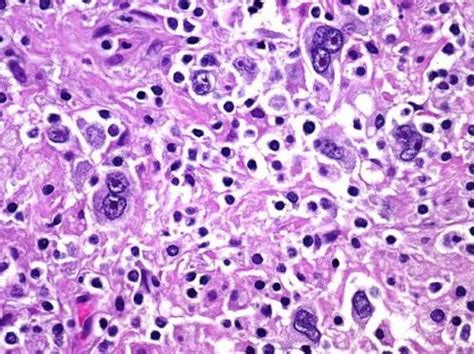

Entre os linfomas, é o tipo mais incidente na infância. Normalmente, essa diferenciação é definida pelos patologistas de acordo com os resultados da neoplasia na biópsia. Linfomas são neoplasias malignas (crescimento tumoral das células) que se originam nos linfonodos (gânglios), muito importantes no combate às infecções. O linfoma não hodgkin (lnh) é um tipo de câncer que tem origem nas células do sistema linfático e que se espalha de maneira não ordenada. Os avanços no tratamento dos linfomas não hodgkin com o uso cada vez mais frequente da imunoterapia.

Normalmente, essa diferenciação é definida pelos patologistas de acordo com os resultados da neoplasia na biópsia. Os linfomas não hodgkin menos agressivos são compatíveis com uma longa sobrevida, enquanto os linfomas não hodgkin mais agressivos podem ser rapidamente fatais sem tratamento. Linfoma não hodgkin ( lnh ). Aunque el linfoma de hodgkin puede comenzar en cualquier lugar, se origina con más frecuencia en los ganglios linfáticos de la parte superior del cuerpo. Sem estreitar mais, o rótulo é de utilidade limitada para pessoas ou médicos. Representa 30% dos linfomas não hodgkin e é o mais comum entre eles. Tumor dos tecidos hematopoético e linfoide. Os autores relatam caso de linfoma não hodgkin em paciente do sexo feminino, de 28 anos, ressaltando o diagnóstico diferencial com formas multibacilares de hanseníase.

O linfoma foi descrito pela primeira vez em 1839 por thomas hodgkin, médico inglês. É possível alcançar a remissão e a cura, entretanto as chances para os dois grupos não são as mesmas. Tumor dos tecidos hematopoético e linfoide. O linfoma não hodgkin é um tipo de cancro hematológico. Não costuma dar sintomas compressivos. Confira na entrevista com o dr. Continuam a ser estudadas as suas causas e a ser investigados. Moleculares, citogenéticas, imunológicas, morfológicas e clínicas distintas. Os linfomas não hodgkin (lnh) são doenças tumorais do tecido linfático e são o tipo de linfomas mais frequente. Os linfomas não hodgkin menos agressivos são compatíveis com uma longa sobrevida, enquanto os linfomas não hodgkin mais agressivos podem ser rapidamente fatais sem tratamento. See more of linfoma hodgkin/no hodgkin honduras on facebook. Em portugal, todos os anos cerca de 1700 pessoas são informadas que têm linfoma não hodgkin (lnh). O linfoma 1 não hodgkin é uma neoplasia 2 do sistema linfático 3 que se caracteriza pela multiplicação descontrolada de células 4 linfáticas, formando tumores.